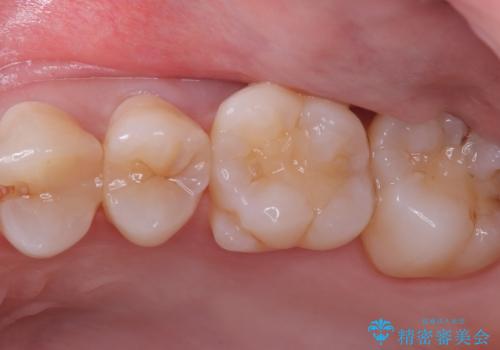

- 主訴:左上真ん中らへんの歯が欠けてしみるので治したい

審美性、適合性の良いセラミックインレーでのやり替えとなりました。

左上4近心に実質欠損を認め、遠心から咬合面にかけてはCR修復が施されていたため、MODインレー窩洞としました。

インレー接着操作時はラバーダム防湿を行っています。